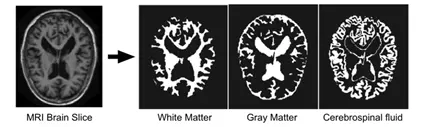

医学图像分割主要处理的是医学领域所涉及到的各种图像的分割问题,比如常见的核磁共振(MRI)扫描图像。其主要任务是,从这些医学图像中分割出兴趣区域,比如特定器官部位、兴趣目标(如肿瘤)等。

1. 脑组织预分割(前背景分割)

为了实现相对准确的分割,有几种常用的MRI数据预处理手段,其中一个重要操作是背景体元移除。其目的是提取脑部组织,并将其与可能与脑部区域存在亮度重叠的非脑部组织(比如脂肪、头骨、脖子等)分离,从而帮助脑区域内部的分割。